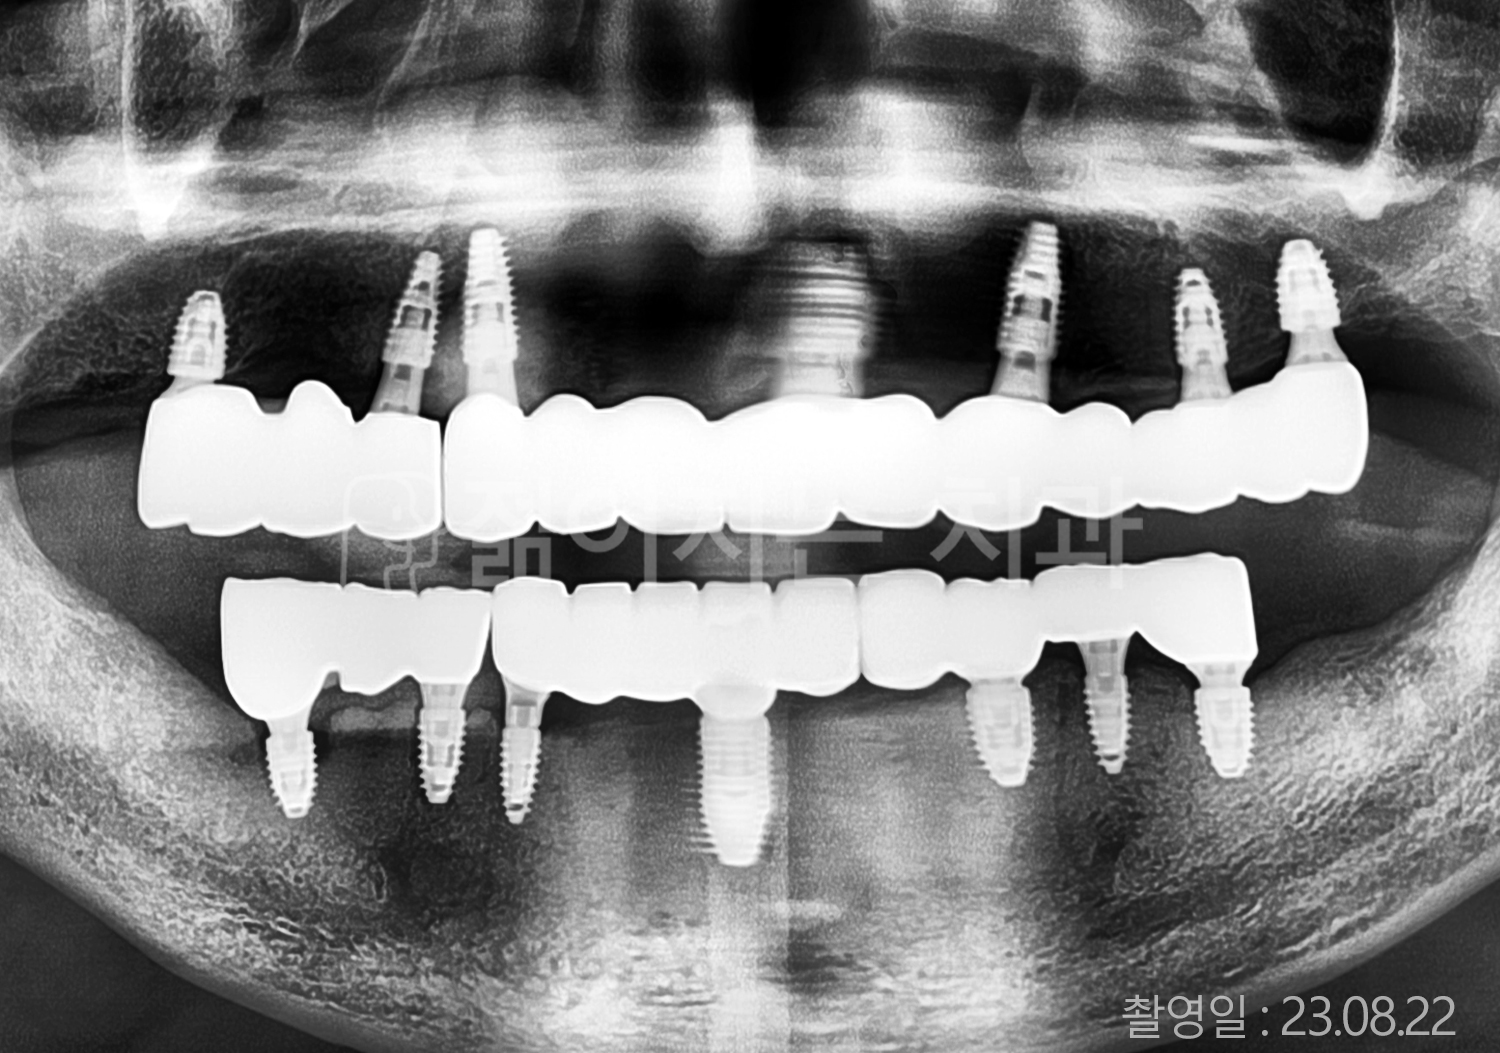

• 50대 전체치아 10개 이상 임플란트